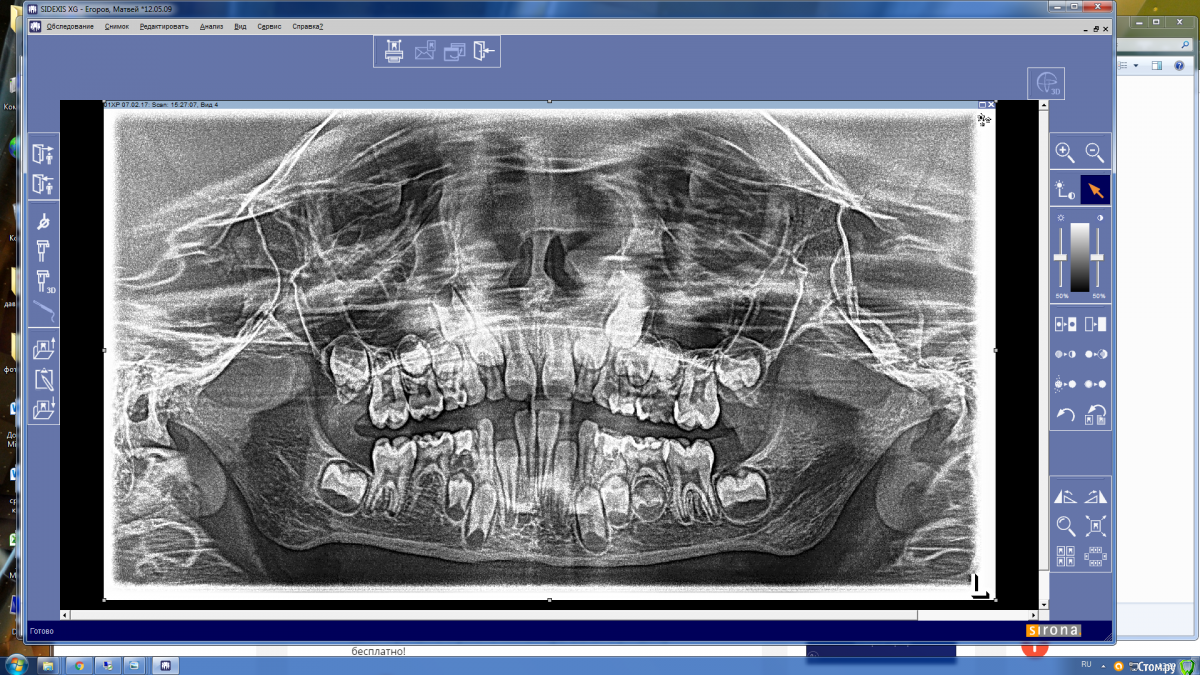

Давлетшин Опубликовано 15 мая, 2017 Поделиться Опубликовано 15 мая, 2017 (изменено) Есть такое слово НАДО. И надо делать ОПТГ в 6-7 лет. Здесь должна быть работа с рентгенологом. Можно отправлять снова и снова на снимки., пока не научится делать, с первого раза. Пусть рентгенолог объяснит позицию " чтобы не облучать". только цифрами и норм. актами. ну а потом и расстрелять можно, только не вы расстреливайте, а родители, за работу спрос с ВАС, а как вы можете сделать качественную диагностику и лечение без снимков. Вообще мне кажется на форуме, надо как то писать, когда задается вопрос, кто в каких условиях работает. может и более правильные рекомендации давали бы. Я дам одну рекомендацию. После 6-7 лет всех на ОПТГ. хоть за 100 км. через 15-20 ОПТГ пойдут"неожиданности" и еще больше укрепитесь в нужности исследования. На десерт неожиданность. Причем подозрение как то интуитивно вышло. Коментировать фото "какой я хороший/плохой, почему без кофера?" не буду. Скажу что был индикатор. И по вашему профилю ВЫ из Молдовы. интересно на одном ли языке мы говорим? Я про молочные премоляры. Мы в России то по разному думаем хотя программа в институтах одинаковая. Изменено 15 мая, 2017 пользователем Давлетшин 1 Ссылка на комментарий

Brigita Опубликовано 15 мая, 2017 Поделиться Опубликовано 15 мая, 2017 кстати - да. Вот веская причина. А мог бы и удалить по возрасту Ссылка на комментарий